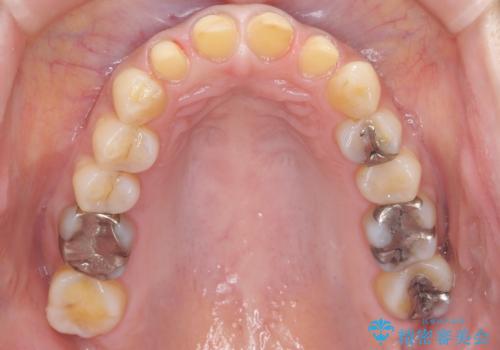

- フルジルコニアクラウン・仮歯 9.9万円×4費用は治療当時の料金となります

適合の良い被せ物が入りました。

樹脂の素材とは違い、セラミックやジルコニアの素材の被せ物は劣化をしません。また、虫歯の再発リスクも低くなります。

形、色、共に満足して頂けました。